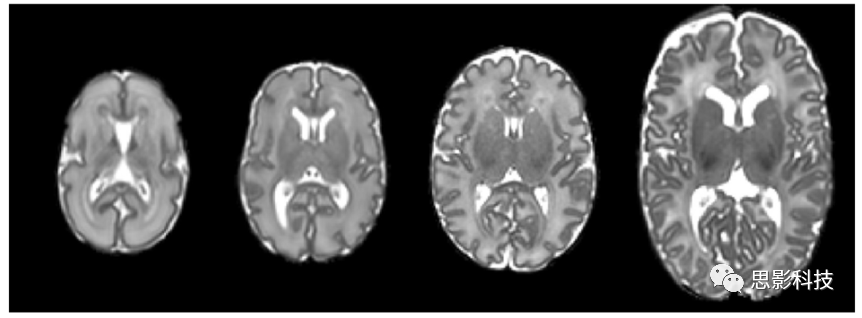

d) 由于在此期間大腦的快速發(fā)育,圍產(chǎn)期大腦的形狀和結(jié)構(gòu)外觀差異很大。皮質(zhì)帶迅速折疊并形成深的灰質(zhì)結(jié)構(gòu)。此外,WM髓鞘形成在大腦發(fā)育過程中是一個持續(xù)的過程,在不同的WM區(qū)域逐漸明顯。由于不同掃描年齡的受試者在解剖學(xué)特征上存在這些差異,因此對其進(jìn)行精確的定位具有挑戰(zhàn)性。圖4展示了在新生兒大腦中隨著掃描年齡的增加所發(fā)生的變化。

4所示。分別在PMA 28周、32周、36周和44周時獲得新生兒大腦T2 MR圖像(從左至右)。